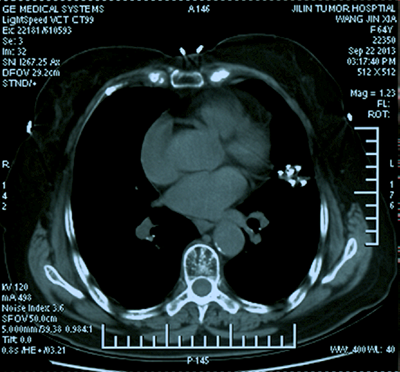

![]() | ![]() |

| (肝癌的消融治疗) | (肺癌的消融治疗) |